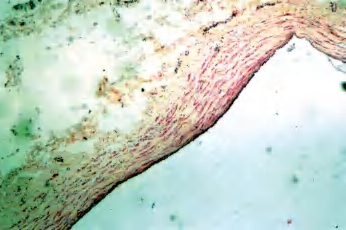

静脉可分为大静脉、中静脉、小静脉和微静脉,管壁结构的变异比动脉大,大致也可分为内膜、中膜和外膜3层,但界限不如动脉明显。静脉壁的平滑肌和弹性组织不如动脉丰富,结缔组织成分较多,故切片标本中的管壁常呈塌陷状,管腔变扁或呈不规则状(图2-15)。

图2-15 静脉自内向外为内膜、中膜、外膜